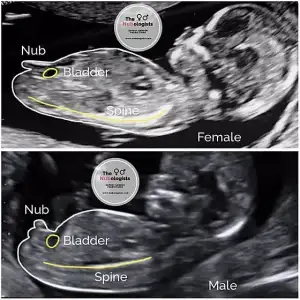

Keseden tutunduğu yere göre tahmin ettiğinizde de oğlunuz demiştiniz :)O cinsel organı oluşacak bölgedeki gördüğüm beyaz parlaklık nub ise, bir kızınız olacak

Nub teorisi

Kimler kimler yazdı?Benim de kesem erkek gibi, nubu belli değil. Fakat hem erkek hem kız dediler bana. Sanırım keseye göre hareket etmeyeceğim. Fakat sizde bir nub görünüyor ama erken haftalar daha bu yani bebeğin duruşundan da paralel durmuş olabilir bu ultrasona göre de bebek kız görünüyor. Rabbim sağlıkla nasip etsin. Bazıların bu arada keseye göre konumu tutmuyor hatta nubta tutmuyormuş. Sizinki de benim bebiş gibi olabilir belki kendini göstermezKeseden tutunduğu yere göre tahmin ettiğinizde de oğlunuz demiştiniz :)

Ben pek nub’tan anlamıyorum canım 5-6-7 haftalarda olan ultrasonu varsa ramziye göre anlıyorum sadeceAy rica etsem bana da bi bakar mısınızvideodan fotoğraf aldığım için çok net olmayabilir 12.haftam :)

Anlıyor musunuz nub teorisindenSizin ultrason fotografinizda birinci bacak arası resmini erkeğe ikinci bacak arası resmini de kıza benzettimdaha tecrübeli arkadaşlar yorum yapabilir

birincisinde bariz çıkıntı var gibi duruyor ama ikincisinde birşey gözükmüyor.

Burda 11 12 hafta arası , videodan aldım resımleri net değil ama :))Pek sayılmazkendi bebisimi erkek olarak yorumlamiştim kız bebişim olacak.daha çok ultrasondaki bacak arası fotoğrafları yorumlamak daha kolay oluyor.sizin zaten haftası 7-8 haftaya nub için çok küçük

Net olmadığı için hiç emin olamadım ama birinci resimde gördüğüm nub ise eğer kız bebeğe benzettim.bacak arası fotoğrafi yok mu ?belki daha tecrübeli arkadaşlar anlayabilir cinsiyetiniziBurda 11 12 hafta arası , videodan aldım resımleri net değil ama :))